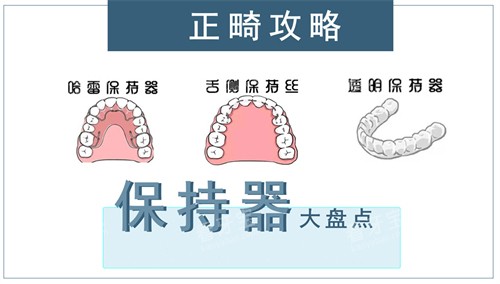

医院名称金属托槽自锁托槽隐形矫正人民口腔8000元起8000元起19800元起(时代天使)贝壳口腔4880元起--兆博口腔8000元起8000元起19800元起(时代天使)欢笑口腔4800元起7800元起8800元起(全隐形)省钱小贴士: 贝壳口腔和欢笑口腔的金属托槽矫正价格较低,兆博口腔和人民口腔的隐形矫正价格相近。如果预算有限,可以选择金属托槽;如果追求美观,隐形矫正是不错的选择。